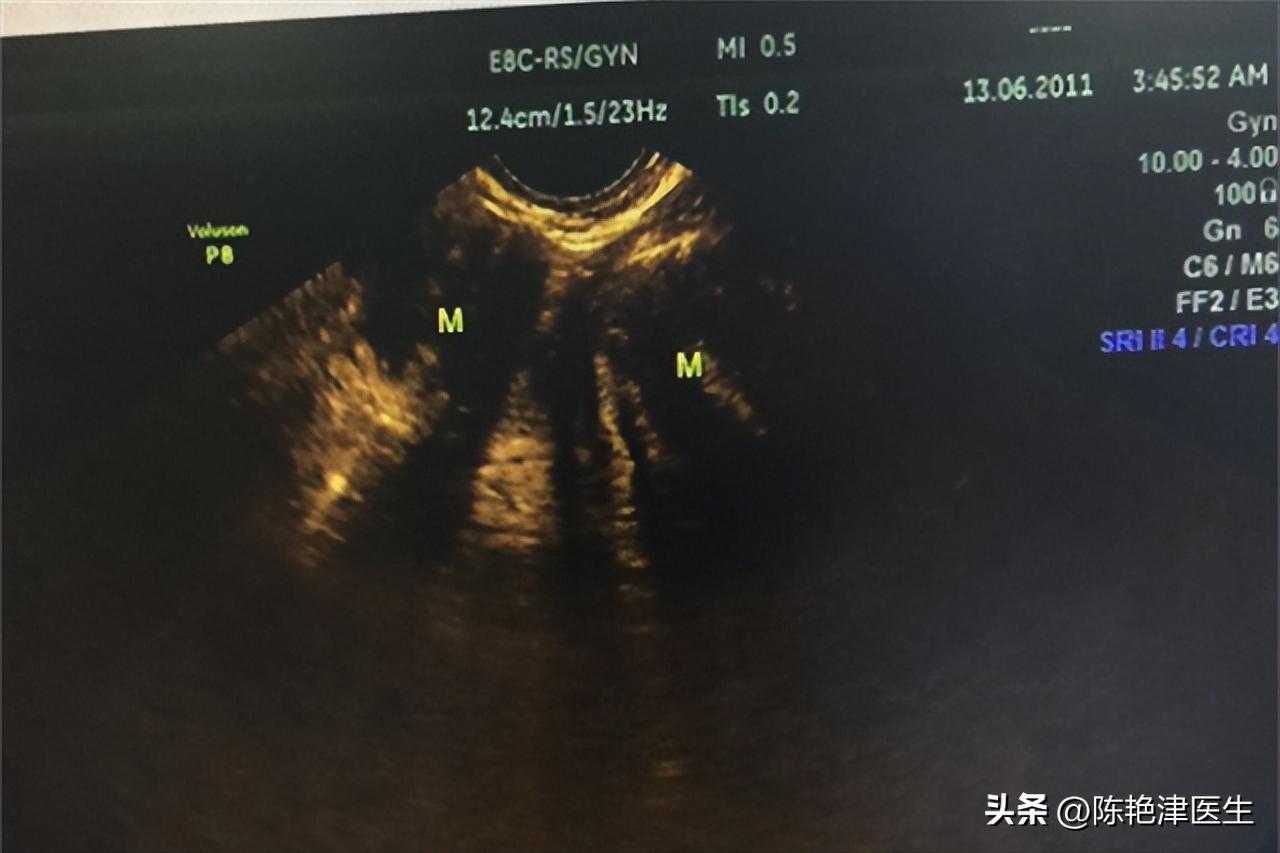

于是我四天前在门诊见到了李女士,简单了解她的病史后,对她的家庭、工作和生育情况作了一个详细的询问。 发现李女士家庭环境不太好;自己在银行上班的压力也很大;怀孕过2次,剖宫产1次(下腹部可见一横行剖宫产瘢痕),人流1次。 在了解这些基本的信息后,我建议李女士先做个一个B超,观察一下情况,再做定夺,当天B超检查结果显示:

子宫呈前位、形态轮廓失常。、宫切面内径68×58×96mm,体积增大,实质回声欠均匀, 宫体肌层见多个实性低回声团,较大约51×47×51mm,形状呈椭圆形,内部为低回声,分布不均质,边缘清楚 。

CDFI:未见明显血流信号。内膜厚10mm,受压移位,光整。

根据B超表现,我怀疑李女士可能患有子宫肌瘤,随即安排李女士进行病理活检,就在昨天病理检查确诊: “子宫”平滑肌瘤 ,于是住院行进一步的治疗。